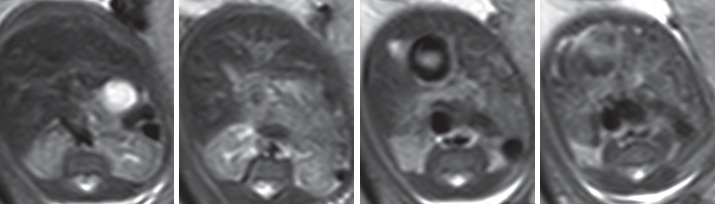

QUESTION NO.49